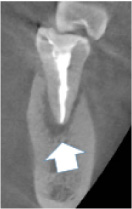

以下は治療のレントゲンです。

矢印の付近、黒い部分が 病気で骨が溶けています。

黒かった病気の部分が なくなりました。